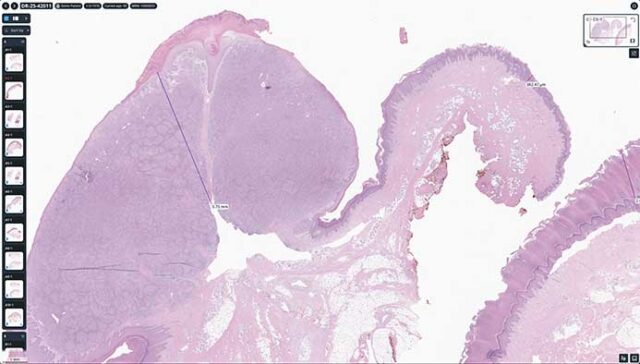

Built with pathologists to deliver an ultrafast cloud-based viewer, flexible worklist, integrated workflows, and state-of-the-art AI.

Techcyte Fusion: The unified anatomic and clinical pathology AI platform

What to expect from the Techcyte platform